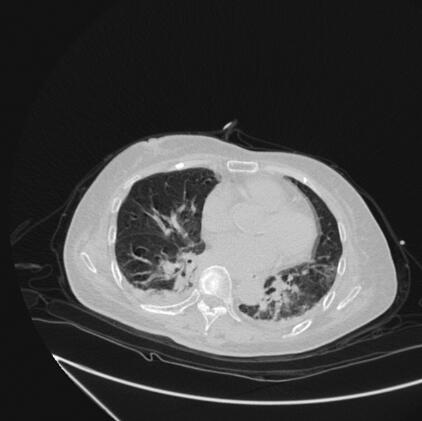

辅助检查:胸、腹部CT示双下肺炎(图1、图2)。心电图示窦性心动过速。血常规:WBC 29.05×109/L,N 88.0%;血气分析:pH 7.383,PO2 54.3mmHg,PCO2 24.9mmHg,SPO2 87.0%;心肌钙蛋白-I 14.3μg/L;生化:总蛋白39g/L,白蛋白19g/L,谷丙转氨酶665U/L,谷草转氨酶582U/L,总胆红素22.0μmol/L,B型脑钠肽1863pg/ml,尿素氮11.8mmol/L,葡萄糖10.9mmol/L,血浆乳酸4.3mmol/L,肌酸激酶512U/L,心肌肌酸激酶42U/L,C-反应蛋白197.0mg/L;糖化血红蛋白14.3%;多次痰培养及血培养均未培养出致病菌。

图1 入院时胸部CT示双肺炎症(肺窗)